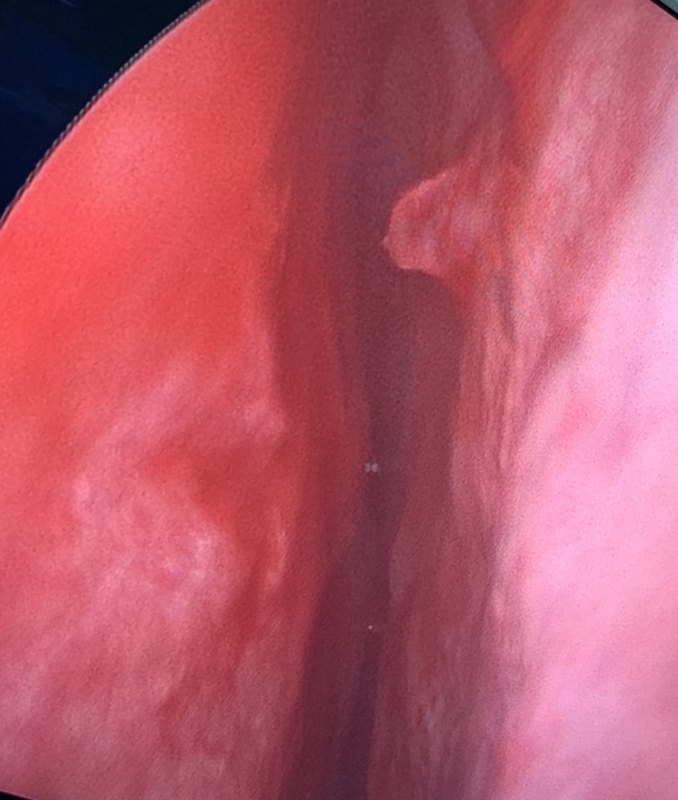

難治性鼻出血是耳鼻咽喉科急、重癥。使用高清STORZ鼻內鏡電凝止血,為鼻腔隱蔽出血點出血的止血治療提供了非常好的手段,避免了反復填塞的痛苦。 鼻腔電凝止血,也就是通過雙極電凝進行止血。對于部分鼻腔前部很容易發(fā)現(xiàn)的血管,患者配合良好的可以局部麻醉下止血。但對于大部分鼻腔深部血管出血或者是頑固性的鼻出血,通常在下鼻道穹窿部或者是鼻中隔嗅裂區(qū)等,需要在全身麻醉下經鼻內鏡反復檢查,才能夠發(fā)現(xiàn)并明確責任血管,然后再予以電凝止血。 手術之前,一定注意以下幾點:1.患者是否有鼻腔鼻竇惡性腫瘤,術前根據(jù)病史評估,必要時行影像學檢查明確。2.術前行凝血功能檢查,如果有凝血障礙性疾病,嚴重的出血傾向,手術治療結果會很狼狽,很失敗。3.是否有頸內動脈瘤或頸內動靜脈瘺。4.嚴重心、肝、腎疾病患者慎行手術。鼻內鏡電凝止血后 鼻中隔出血點